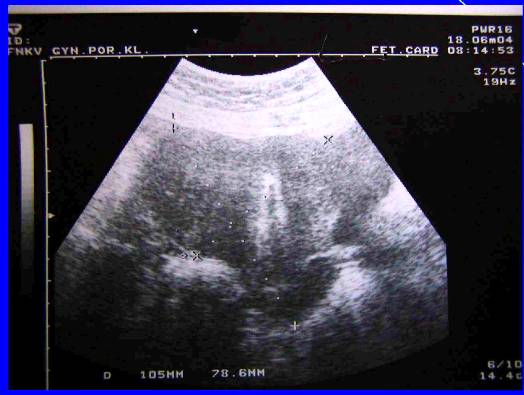

1. Recidiva (generalizace do dutiny břišní) –pac. M.T., tu markery, sono, laparotomia, peroperační biopsie

Recidiva (generalizace do dutiny břišní) –pac. M.T., tu markery, sono, laparotomia, peroperační biopsie

Recidiva(generalizace do dutiny do břišní) ––pac. M.T., sono, laparotomia, peroperační biopsie